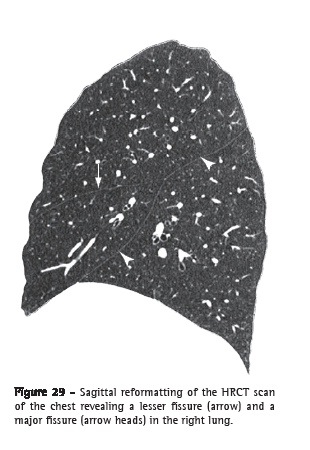

Fissure (fissura or cissura)

Fissure is the invagination of the visceral pleura that covers the outer surface of the lung to the parenchyma.(7) Each interlobar fissure is formed by the juxtaposition of two layers of visceral pleura. In general, we can identify major (oblique) fissures, which separate the lower lobes from the others, and the lesser (horizontal) fissure, distinguishing the middle lobe from the right upper lobe (Figure 29). Supernumerary fissures are frequently found.